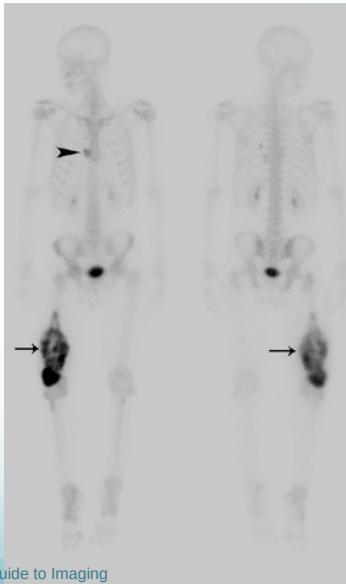

Additional Imaging

- Bone scan:

- Primary lesion

- Metastasis

- MRI very informative